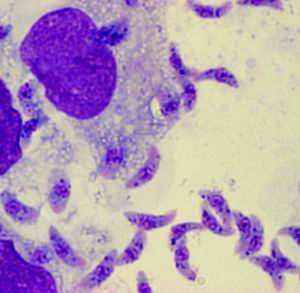

猫科动物会携带一种微生物,学名为刚地弓形虫,它属于原虫类寄生虫,只有几微米大小。孕早期宫内感染弓形虫能导致流产,孕中晚期则损伤胎儿的大脑和视网膜;还有一部分隐性感染,出生后表现为健康新生儿,数月或数年后出现眼睛和神经系统的病变。宫内感染弓形虫是人类最严重的先天性感染疾病之一。